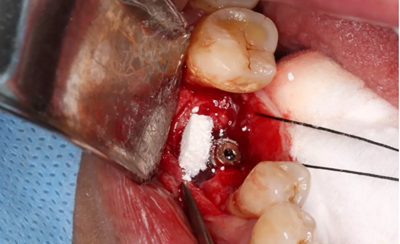

6、牙槽嵴保存術(shù)過(guò)程:拔牙及位點(diǎn)保存

(攝于2016年8月31日)

14、植骨手術(shù)過(guò)程

刮除肉芽組織及種植體表面清潔后,種植體唇側(cè)骨缺損區(qū)植入人工骨粉。

(攝于2017年8月10日)